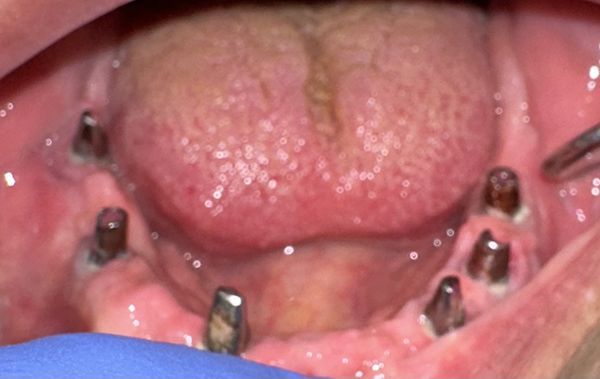

CASO NUMERO 1: GIOVANE PAZIENTE SENZA INCISIVI SUPERIORI (EDENTULIA PARZIALE)

La paziente era portatrice di apparecchio mobile (protesi mobile) da anni, risolto con implantologia. La paziente tornerà ad avere un sorriso disinvolto e mangiare bene, come se avesse i denti naturale, senza la paura che la protesi si sganci nei momenti più inopportuni.